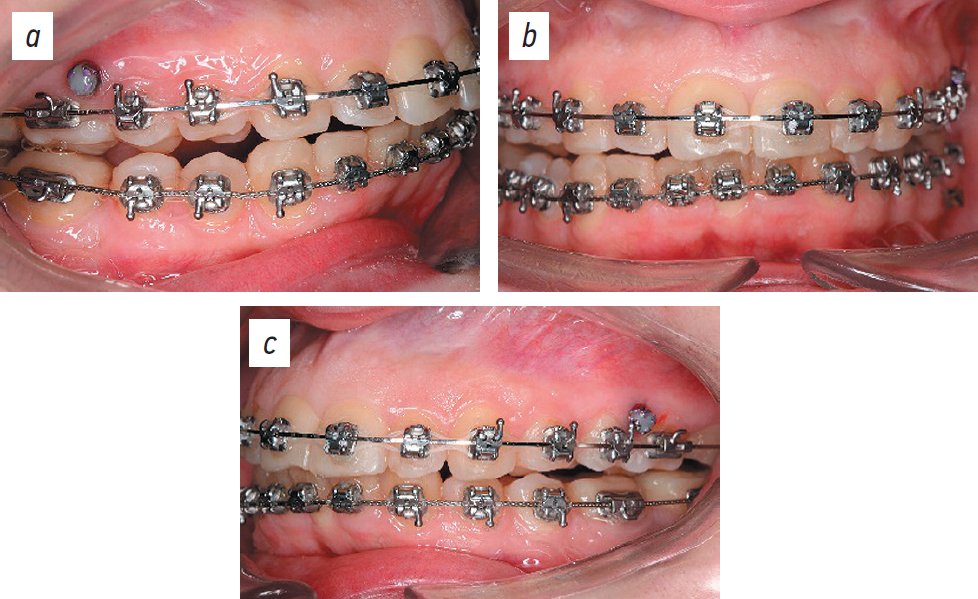

Empower braces (CuNiTi 0.14; American Orthodontics, USA) were installed on the maxilla (Figs. 10, 11).

Fig. 10. Dental arches after braces placement, lateral right projection (a), posteroanterior projection (b), left side projection (c).

Рис. 10. Зубные ряды после устновления брекет-системы: боковая правая проекция (a), передняя проекция (b), боковая левая проекция (c).

One month after braces were installed on the maxilla, nano-osteoperforation of the roots of teeth 7, 6, 9, 10, and 11 (ISO designations 12, 13, 21, 22, and 23, respectively) was performed, and a BioEdge 16×16 archwire was installed (Fig. 12).

Fig. 12. Dental arches after nano-osteoperforations: right lateral projection (a), posteroanterior projection (b), left lateral projection (c).

Рис. 12. Зубные ряды после нано-остеоперфораций: боковая правая проекция (a), прямая проекция (b), боковая левая проекция (c).